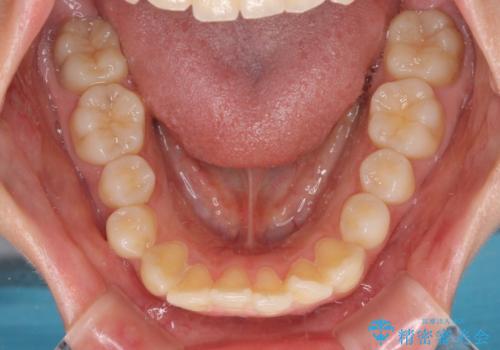

上下ともに歯列が前方に突出していたため、上下左右の第一小臼歯4本を抜去し、ワイヤー装置による矯正治療を行うこととしました。

上下左右4本抜歯する場合には、通常2年から2年半ほどの期間を要しますが、僅か1年半で終了することができました。